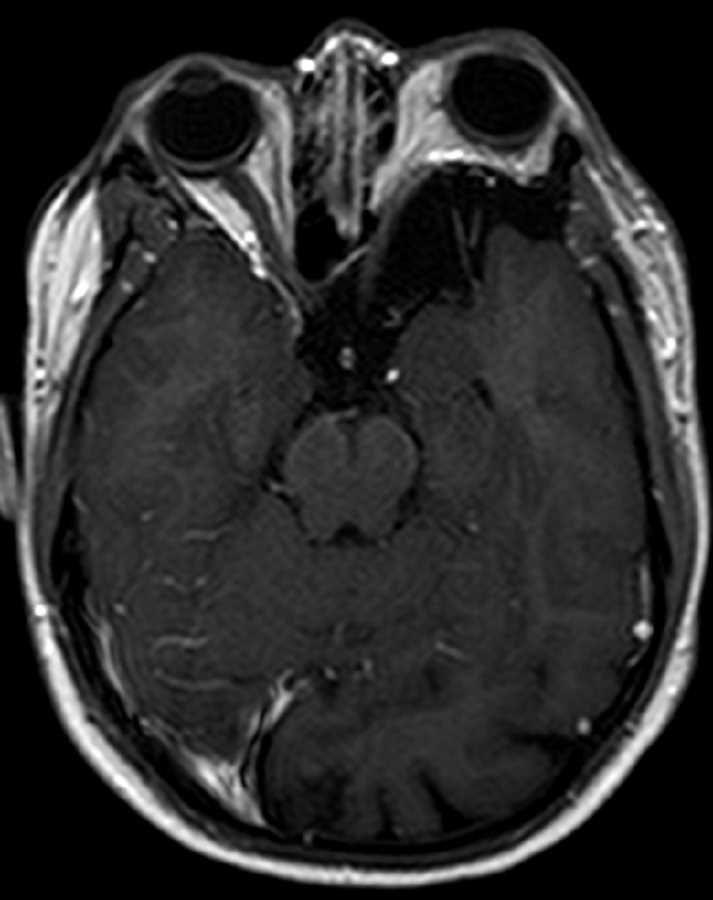

Sphenoid Wing Dysplasia

These images demonstrate deficiency of the left sphenoid wing with bulging of the meninges and peritemporal CSF into the posterolateral aspect of the orbit resulting in moderate left proptosis in this patient with a history of NF-1. There is asymmetric expansion of the left cerebral extra-axial spaces. No associated plexiform neurofibroma is identified. Findings are consistent with sphenoid wing dysplasia which is seen in less than 10% of patients with NF-1. Patients with this deformity may present with pulsating exophthalmos and diplopia. Management usually consist of surgical reconstruction.